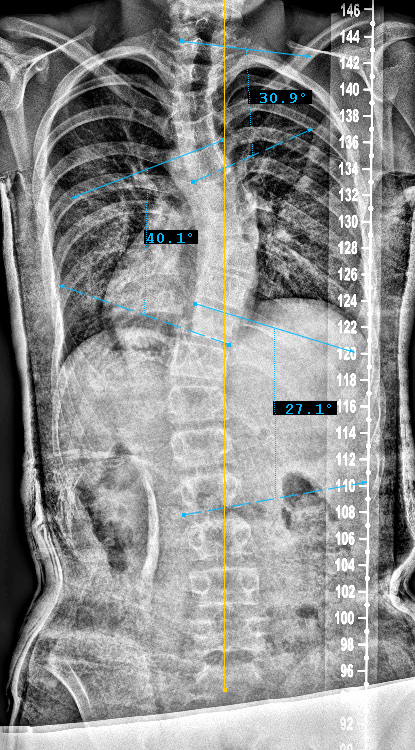

Curve Type 2

proximal thoracic curve structural, main thoracic curve major, lumbar curves non-structural

Lumbar modifier B

CSVL touches pedicle of apical lumbar vertebrae (ALV)

Sagittal Modifier ( + )

T5-T12 in the >40o range

Therefore, Classification is Type 2B+

Preop PA View